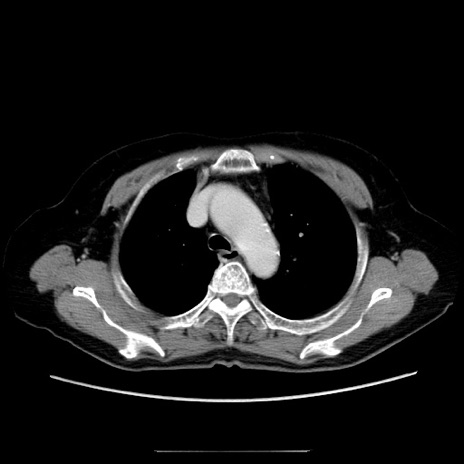

症例5(横断像)

【症例】70歳代女性

【主訴】お腹が張る

【現病歴】1週間くらい前から腹部膨満の自覚あり。昨日夜から増悪したため、本日救急外来受診。

【身体所見】意識清明、BT 36.5℃、BP 165/106mmHg、HR 80bpm、SpO2 98%、腹部:膨満、軟、自発痛・圧痛なし、触診にて不快感あり、腸蠕動音:減弱

【データ】WBC 12600、CRP 1.04